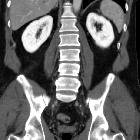

Hypovolemic

shock with subtle imaging signs: systemic capillary leak syndrome. Most of the collapsed colon showed diffuse, moderate circumferential mural thickening (thin arrows) with mucosal enhancement and mural hypoattenuation suggesting submucosal oedema.

shock with subtle imaging signs: systemic capillary leak syndrome. Portal venous phase images showed marked, bilateral symmetric and homogeneous enhancement (average 320 Hounsfield units compared to 35 HU precontrast attenuation) of the renal parenchyma.